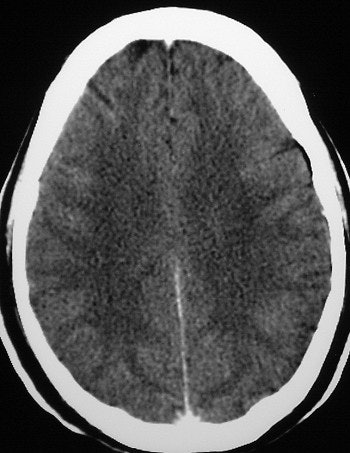

Axial cuts at the levels of the lateral ventricles and centrum semiovale (mAs 335, kv 120). A loss of GWMD is shown in a 51-year-old comatose patient with exertional HS in comparison to good GWMD in a 50-year-old patient, below. Images courtesy of Dr. Oded Szold.

According to the results, "all six patients demonstrated severe loss (grade 2-3) of the GWMD. None suffered from CNS bleed or displacement of anatomical structures. The difference on CT between the gray and the white matter is thought to be due to the higher content of water and lower content of lipids in the gray matter. This results in higher oxygen and lower carbon concentrations in the gray matter, causing increased photoelectric absorption," they said.